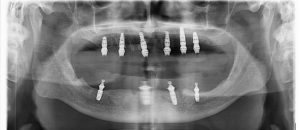

Impression 3 d des 2 bridges transvissés provisoire et pose.

A peine 5 h après le début de la chirurgie le patient peut repartir avec 2 bridges provisioires .

Le numérique, la chirurgie guidée et l’impression 3d nous permette de réduire énormément les temps opératoires et de laboratoire .